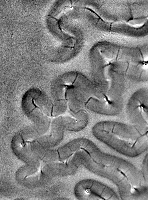

| gradient echo phase image of central sulcus, 220x220x1000 micron,

scan time 12 minutes |